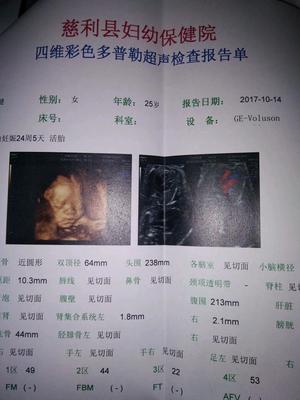

在这么多的产前检查项目中,在孕六个月左右做四维彩超是非常重要的,因为医生可以通过屏幕直观地观察到胎儿的面部、心脏、以及其他内脏器官,胎儿的所有器官在孕22周就已经发育完成,孕24周就可以清晰地看到。如果有什么异常,是可以发现的。

建议孕20周后做胎儿四维彩超。2.胎儿的四肢和主要器官在怀孕20周后已经全部发育完成。最佳检查时间为孕24周、28周,因为这个阶段胎儿结构已经形成,胎儿大小和羊水适中,胎儿骨骼回声相对较小,图像清晰。所以这个时期是胎儿畸形检测最理想的时期,通过检查可以排除大部分畸形。四位彩色多普勒超声使用的仪器称为“四维彩色超声诊断仪”。

一般来说,妊娠2428周是四维彩超的最佳时间,因为胎儿24周左右是大脑快速发育的时期,这期间胎儿结构已经形成,胎儿大小和羊水适中,在子宫内的活动空间较大,胎儿骨回声的影响相对较小,图像相对清晰。四维超声在三维超声的基础上具有实时动态效果。准爸爸和准妈妈可以通过屏幕见证宝宝在妈妈肚子里的运动、呼吸、吞咽、打哈欠、吐舌头等生理活动,非常直观。